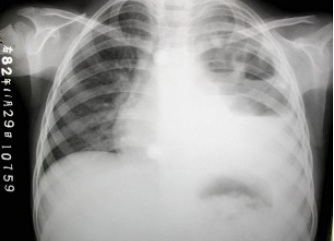

178、单项选择题

男,38岁,感胸闷气逼2周余,近来加剧,不发热,X线检查如图,最可能的诊断是()

A.右侧肺不张

B.右侧胸膜肥厚

C.右侧大量胸腔积液

D.右侧中量胸腔积液

E.右侧气胸

点击查看答案